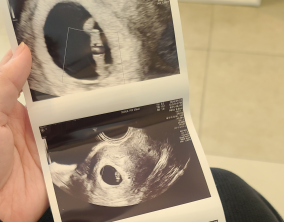

희망의 순간들

믿음 끝에 찾아온 첫 기적

심장소리 이후, 함께 웃게 된 임밍아웃